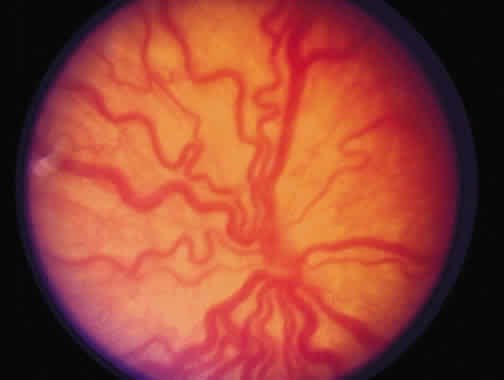

Progressive vascular incompetence, occurring with the changes at the edge of the abnormally developing retinal vasculature, is noted by increasing dilation and tortuosity of the peripheral retinal vessels, iris vascular engorgement, pupillary rigidity, and vitreous haze. When the vascular changes are so marked that the posterior veins are enlarged and the arterioles are tortuous, a plus sign is added to the ROP stage number (Fig. 4). Subsequent to the initial ICROP report, completion of the classification of ROP led to the publication of the classification of retinal detachment.41 Stage 4 was expanded to stage 4A and 4B. Stage 4A (Fig. 5) represents extrafoveal retinal detachment, which is a concave traction type of retinal detachment in the periphery without involvement of the macula. These detachments generally are located in anterior zone II or III. Stage 4B (Fig. 6) is a partial retinal detachment including the fovea, which usually extends in the form of a fold from the disc through zone I to involve zones II and III. Stage 5 retinal detachments are total and always funnel shaped. Stage 5 is subdivided based on the shape of the funnel. The funnel is divided into anterior and posterior parts, allowing for four subdivisions, depending on whether the funnel is open or narrow in both parts of the funnel.

Fig. 4. Marked “plus” disease.